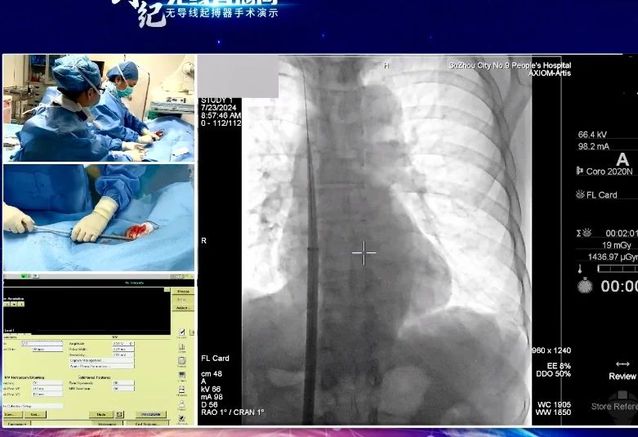

7月24日,“创势纪·无线直播间—苏皖区域无导线起搏器手术演示”在线上举行,苏州九院心血管内科主任吴雁鸣参与手术演示,助力提升区域心血管病防治水平。本次活动由江苏省医学会心血管病学分会副主任委员、苏州市心血管病学分会主任委员、苏州大学附属第一加勒比扑克 心内科主任蒋廷波主持,汇聚了一大批专家教授开展手术演示和线上探讨,通过学术交流积极推动苏皖地区心血管病防治水平的进一步提高。

早在2021年,苏州九院心血管内科就积极引入和开展无导线心脏起搏器植入术,是我区首家成功独立开展无导线起搏器植入手术的加勒比扑克 。心血管内科主任吴雁鸣是我区首位独立无导线起搏器术者,目前已成功独立植入近30例,受益人群大多为高龄老人,其中年龄最大的患者接受手术时已经103岁。